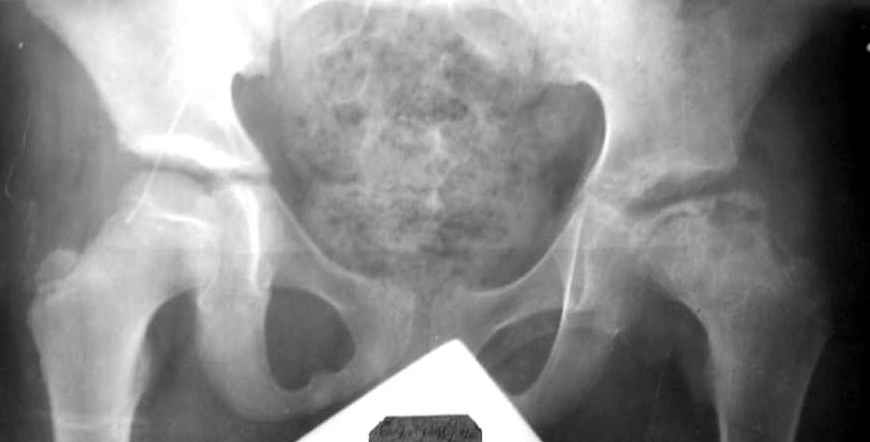

Мальчик 12 лет. Год назад по поводу асептического некроза, в субкапитальную область пересадил аутокостный трансплантат, взятый из Spina iliaca an.sup., на мышечной ножке m.sartorius.

На данный момент движения в суставе в полном объеме и без болезненны, ходит с помощью одного костыля, хотя, может спокойно передвигаться и без дополнительной опоры. Учитывая дисплазию, рекомендовал один костыль пока не бросать. Конечно, чем дольше он будет ходить на костылях, тем лучше для сустава, но ему всего 12, и он как все нормальные дети хочет бегать, прыгать, играть в футбол.Посоветуйте, пожалуйста, как быть?Заранее благодарю, Алишер.

На представленной рентгенограмме (лев. сустав) типичная картина последствия болезни Пертеса с уменьшенной высотой эпифиза. Процесс завершился и нет необходимости в дальнейшем использовании доп. средств опоры. Выраженных дспластических явлений нет. Позвольте пациенту жить без особых ограничений, но ежегодно проводите контрольный осмотр. АИФ.